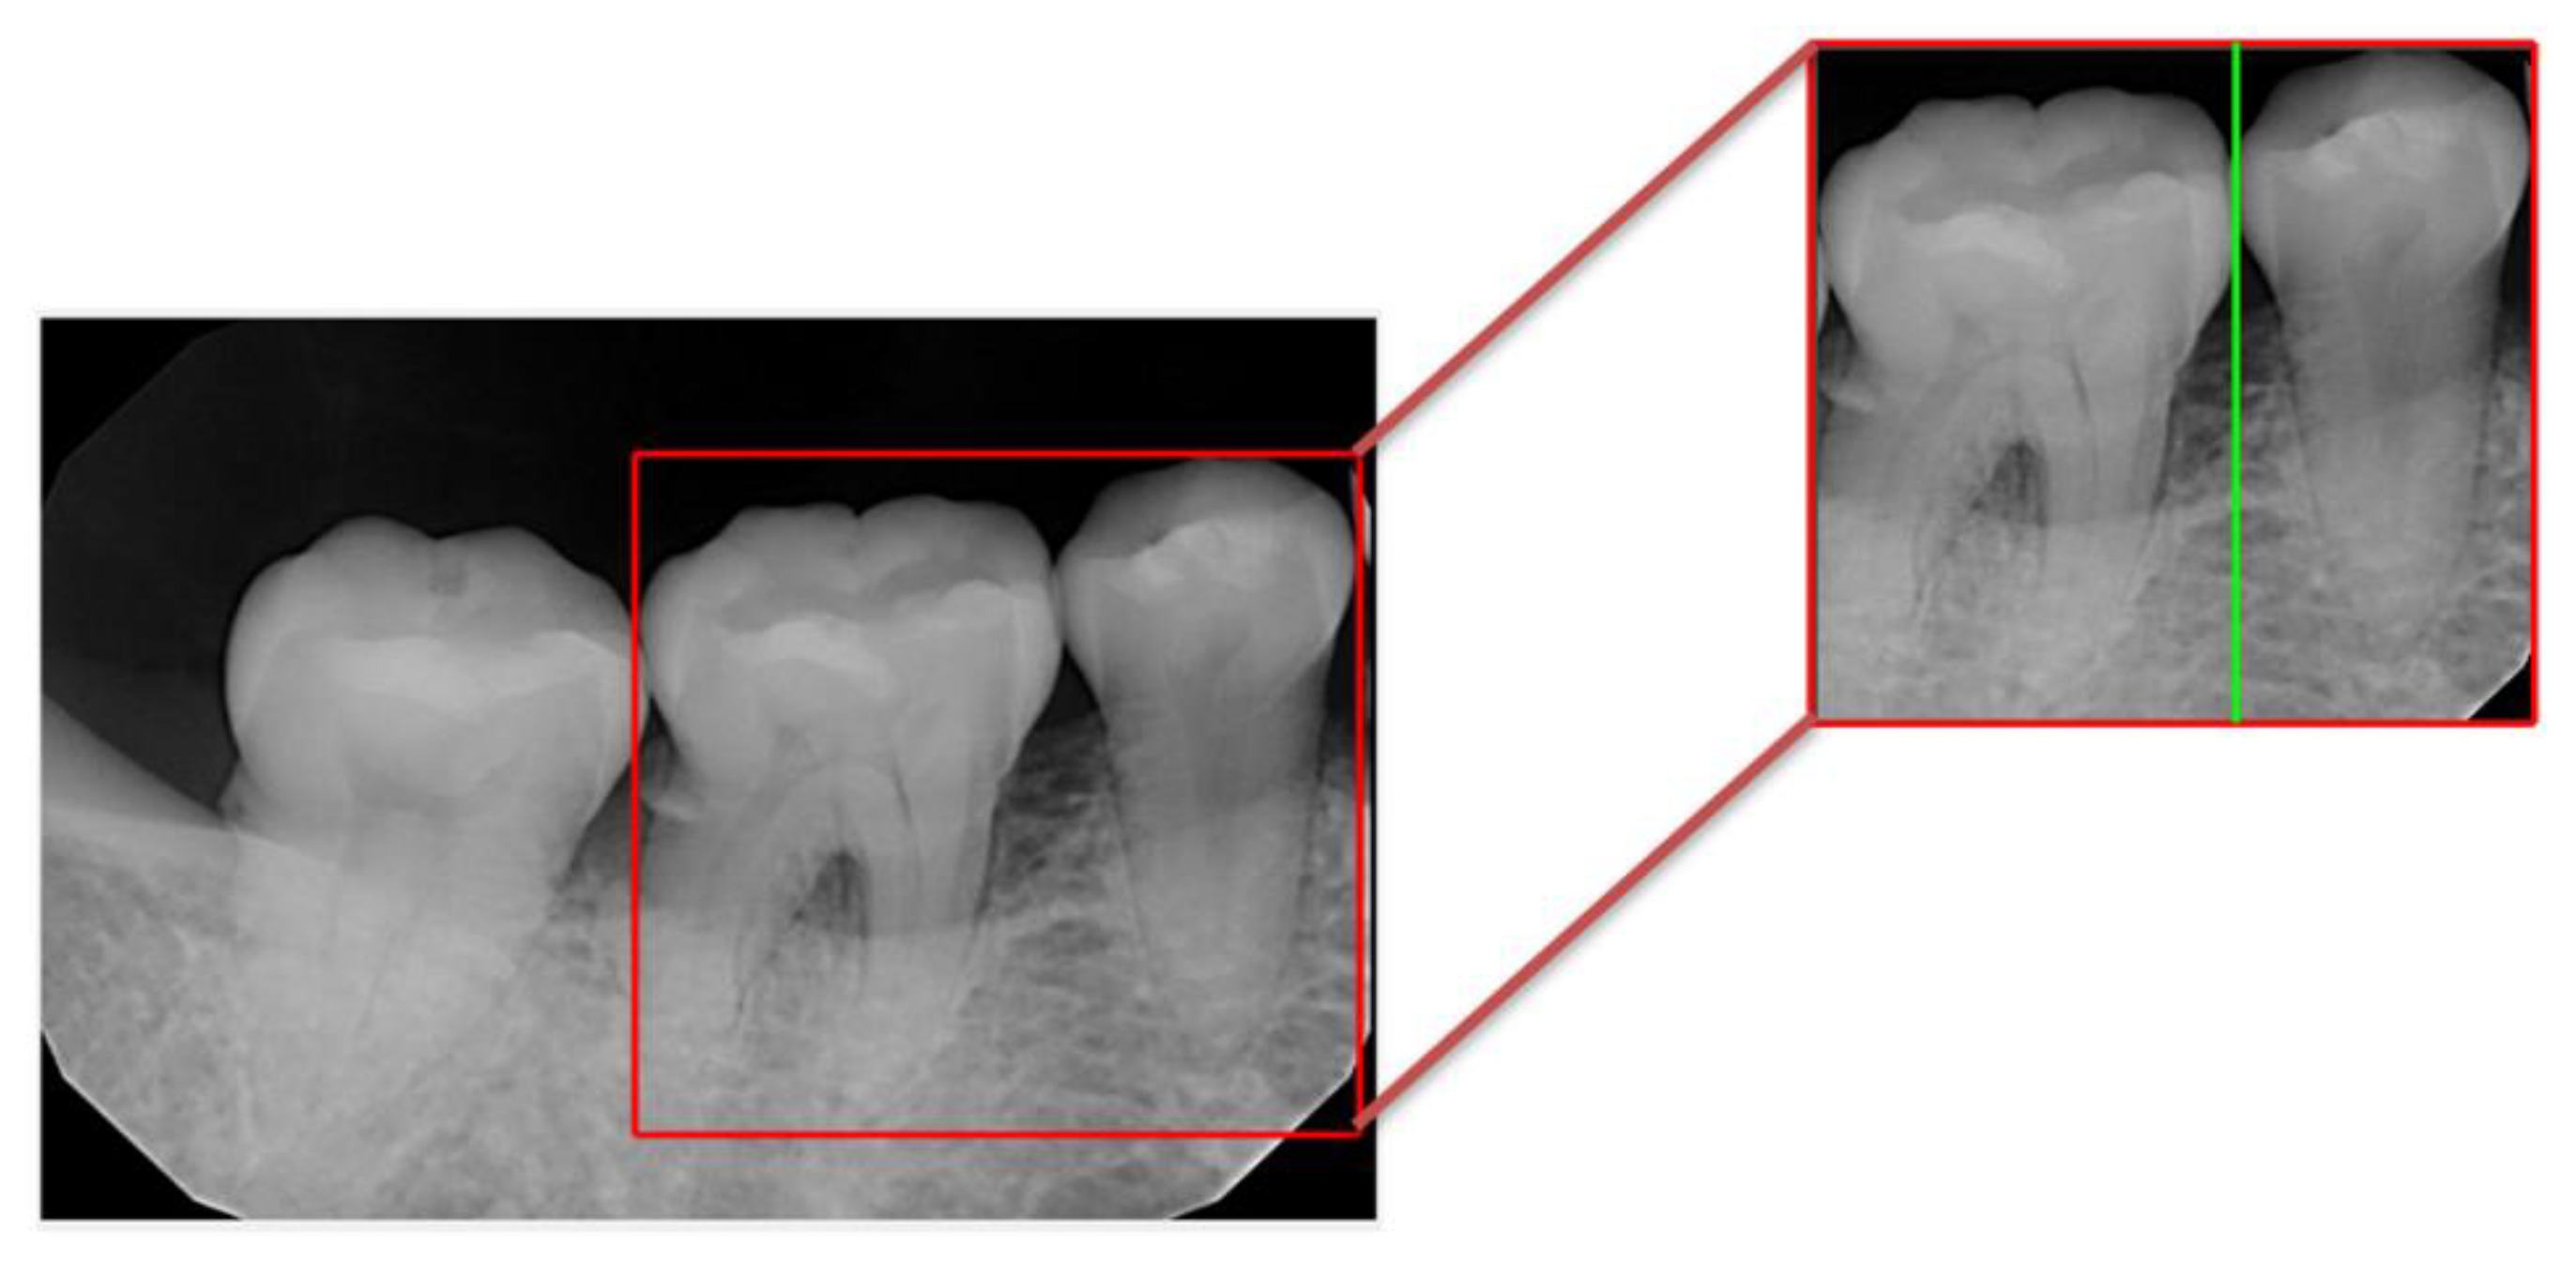

2.2. Image Segmentation

2.2.1. Vertical Projection

2.2.2. Rote Tangent